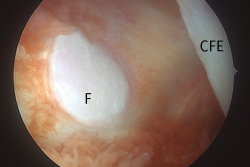

Figura 8. Visión transescotadura, compartimento posterolateral, rodilla izquierda. Imagen de la carilla articular de la fabela, hueso sesamoideo articular incluido en el tendón del gastrocnemio externo. CFE: cóndilo femoral externo; F: fabela.